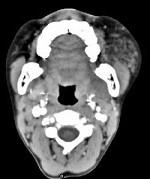

问题 男,12岁,左面颊肿大5年余,局部呈紫红色,CT如图所示,最可能诊断为()

选项 A.蔓状血管瘤 B.血管外皮瘤 C.动静脉畸形 D.慢性腮腺炎 E.下颌下腺慢性炎症

答案 A